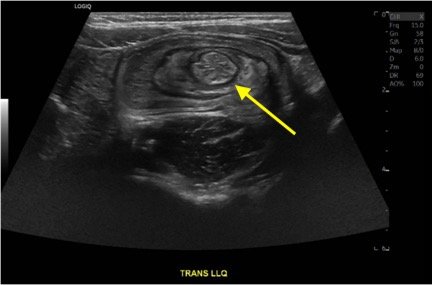

Intussusception is the telescoping of bowel into an adjacent segment of bowel and has an associated risk for bowel ischemia and perforation. The classic triad of abdominal pain, blood in stool, and an abdominal mass is present in less than 40% of pediatric cases and is less common in older children.1 Ultrasound has a high sensitivity and specificity for the diagnosis of intussusception, and once diagnosed, treatment modalities include reduction by either ultrasound or fluoroscopic guided air or hydrostatic enema. The risk of recurrence after successful reduction occurs in up to 12% of pediatric patients and occurs more frequently in older children and children with a pathologic lead point.2 We present a case of a 6-year-old child with colocolic intussusception that was successfully reduced and recurred within five days due to a large colonic polyp.